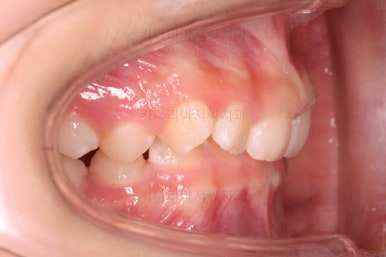

초진 시 입안의 모습입니다.

앞니가 안으로 굽어 들어간 양상인데요. 흔히 "옥니"라고 표현합니다.(뻐드렁니의 반대개념)

전반적으로 치열이 삐뚤삐뚤하고요.

그리고 전반적으로 아래 치열이 윗니에 비해 뒤로 밀려 있어서, 어금니의 맞물림이 좋지 못하고 듬성듬성해 보이는 상황이었어요.

과개교합, 옥니, 앵글씨 2급 부정교합 모두 좋아지고 있어요.

엉성했던 어금니 맞물림도 매우 좋아졌어요.(앵글씨 2급 부정교합 개선)